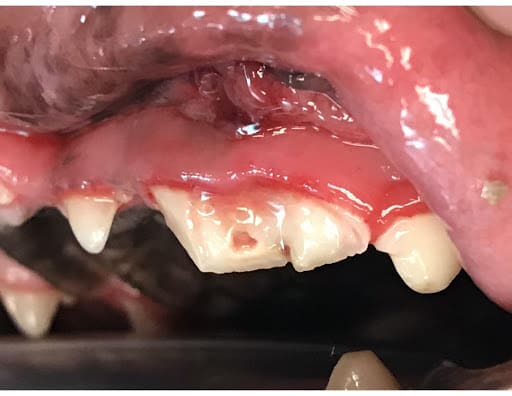

Tooth Fracture with Pulp Exposure

Tooth Luxation from Dental Trauma in Dogs

Tooth luxation in dogs is the partial separation of the tooth from its socket (alveolus). Tooth luxation most commonly occurs when a pet bites on a moving object such as a tire, another animal, or if they suffer blunt trauma to the face.

The most common teeth luxated are the canine teeth. Luxated teeth are treated in one of the following two ways: 1) Return of the tooth to its normal position and placement of an intraoral splint with subsequent root canal therapy or 2) Extraction.

Ideally, the tooth is repositioned within the socket followed by placement of a splint to allow healing of the supporting bone and periodontal tissue. At the subsequent checkup, the splint will be removed. Root canal therapy is completed at this time since the blood supply to the tooth was severed at the time of luxation. This causes the pulp of the tooth to be necrotic (dead). Alternatively, the luxated tooth can be extracted. Root canal therapy is ideally the best option since the pet can avoid a surgical extraction.

Luxated Canine Tooth Luxated Canine Tooth Replaced with Splint